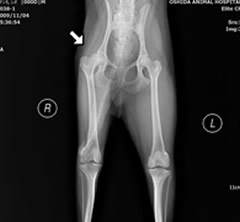

レッグ・ペルテス

無菌性大腿骨頭壊死症

小型の若齢犬に多く、外科的治療が最優先となります。